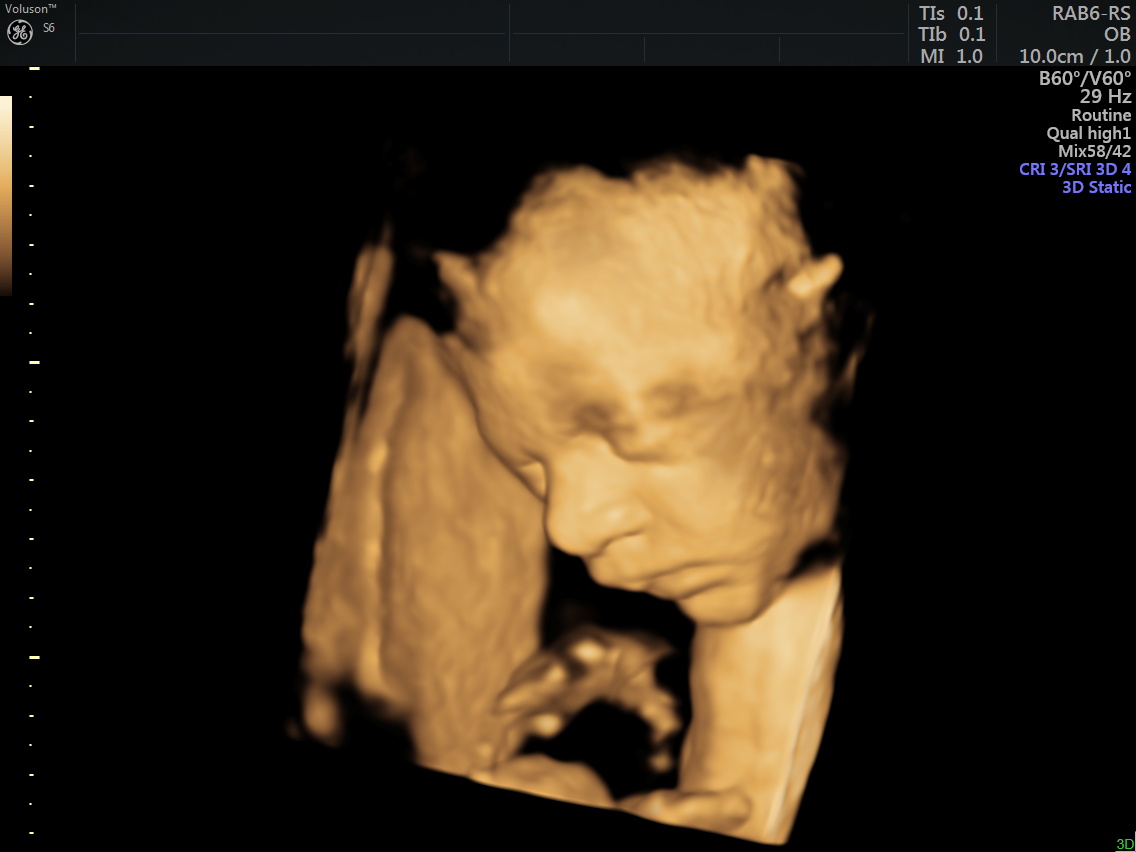

4D (dört boyutlu), Renkli, Ayrıntılı Gebelik Ultrasonu

4 boyutlu renkli ultrason ve 3 boyutlu ultrason aslında aynı anlama gelmemesine rağmen halk arasında , ayrıntılı ultrason, detaylı ultrason , ileri düzey ultrason, anomali ultrasonu , 2. basamak ultrason, ikinci düzey ultrason, renkli ultrason , büyük ultrason , genetik ultrason ile aynı anlamda kullanılmaktadır.

4 boyutlu renkli ultrason cihazı ile çok erken dönemde cinsiyet, yarık dudak, yarık damak, eksik parmak, beyin ve omurilikten kaynaklanan rahatsızlıkların erken tanısı konulabiliyor.